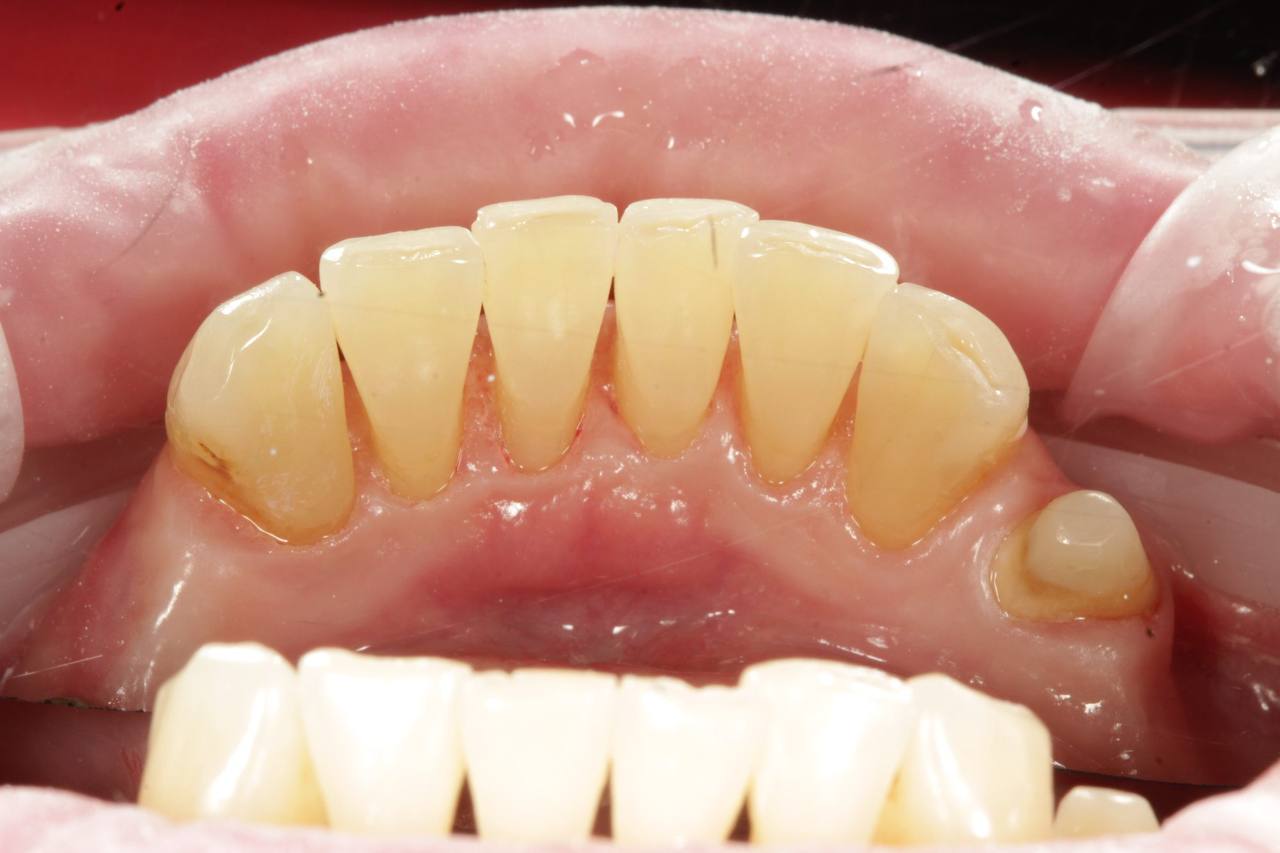

Після

Професійне чищення зубів

Професійне чищення зубів дає прекрасні результати, так як дозволяє не тільки зняти зубні відкладення, але й відполірувати зубні поверхні. Мікробам і харчовим забрудненням складніше прикріплятися до гладкої емалі, тому після процедури швидкість накопичення нальоту на зубах знижується.

Чищення зубів у стоматолога відрізняється максимальною ефективністю, оскільки у фахівця набагато кращий огляд ротової порожнини пацієнта, ніж у самого пацієнта. Стоматолог усуває наліт з усіх ділянок, включаючи ті, які пацієнт не бачить, або до яких не дістає.

Професійне чищення зубів допомагає не тільки природної зубної емалі протистояти мікробам. Час від часу потрібно полірувати та очищати реставрації, встановлені в порожнині рота. Пломби, коронки та вініри, працюють нарівні з натуральними зубними тканинами, але більш схильні до руйнування під впливом мікробів. Однак від того, наскільки вони чисті, залежить їх естетика та довговічність. Не можна ігнорувати необхідність профгігієни й людям, які проходять ортодонтичне лікування. Брекети та інші лікувальні пристрої дуже ускладнюють самостійність гігієнічної процедури.